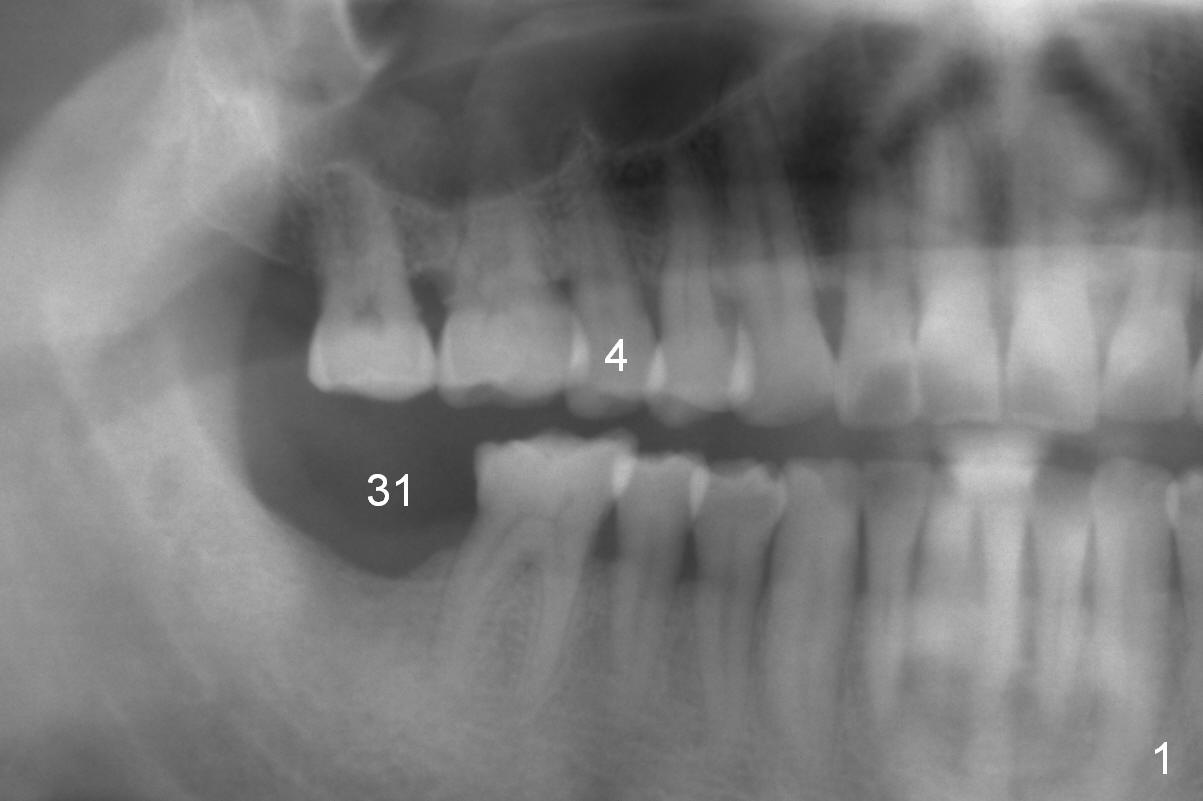

A 61-year-old man (WJ) cracked the tooth #31 after RCT. Four years after #31 extraction, the tooth #4 cracks by itself. The apex of the tooth appears to protrude into the sinus and is closely associated with the sinus septum (triangle: Fig.2,3). An implant will reach the top of the socket for stability (Fig.4 black area). The abutment is expected to be 4.8x4(3) (SM) or 4.5x4(3) (UF) mm. Metronidazole will be used for disinfection of the socket. On returning, he requests #31 implant.